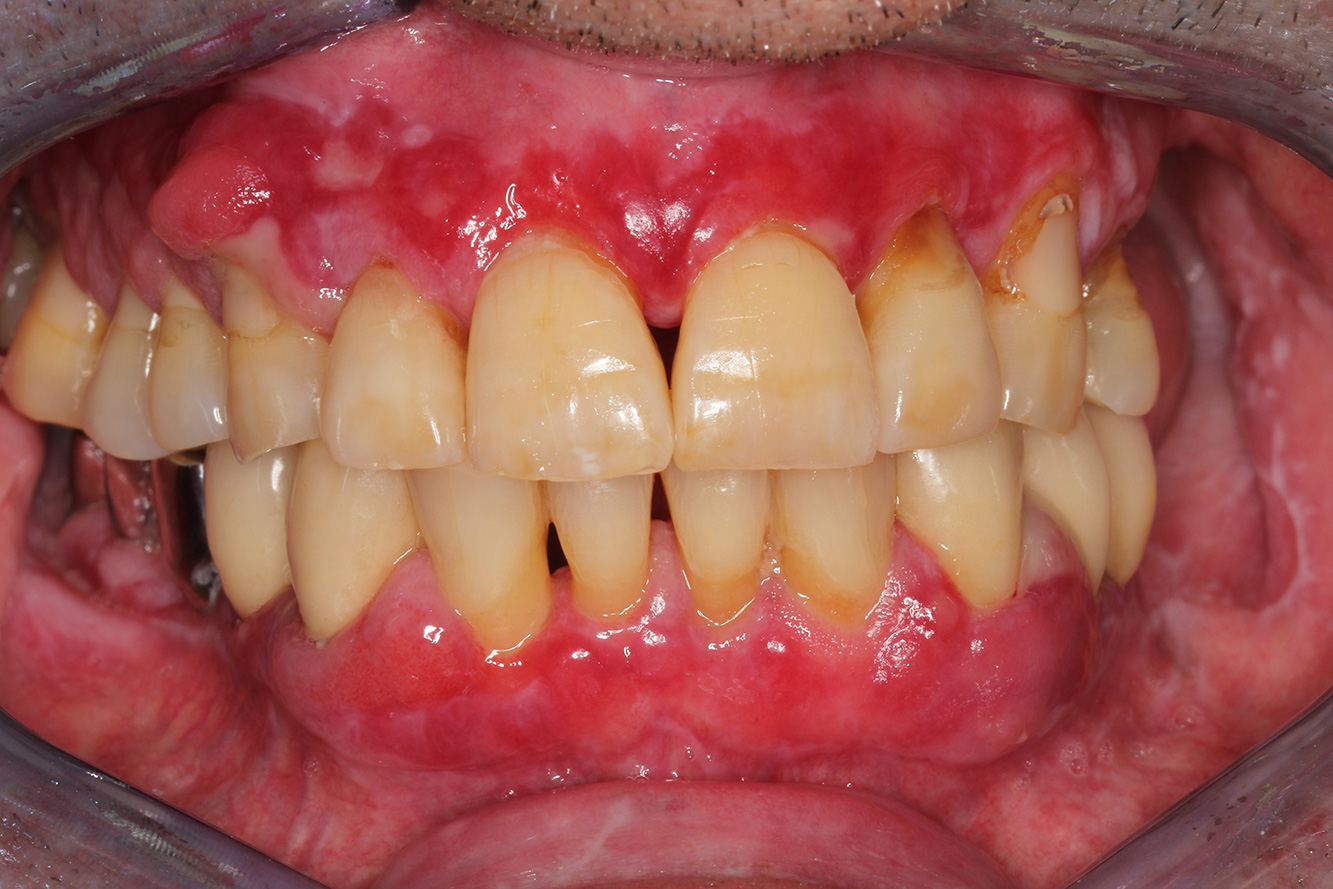

Die gesunde Patientin mit parodontaler Vorerkrankung